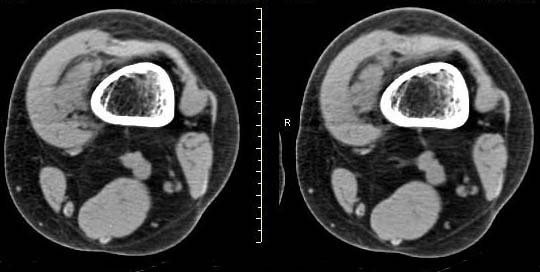

女,24岁,左大腿下部近膝关节处偏内侧有一软组织包块,触之有压痛,平扫示病灶密度不均,形态及轮廓欠规则,无包膜,与周围组织界限不清,增强后显示有明显强化且不均匀强化,本人考虑为该软组织肿块为恶性病变。请大家发表高见!

病灶是有不均匀强化,但病灶与周围组织分界较清,所以性质难定。

病灶是有不均匀强化,但病灶与周围组织分界较清,恶性可能。